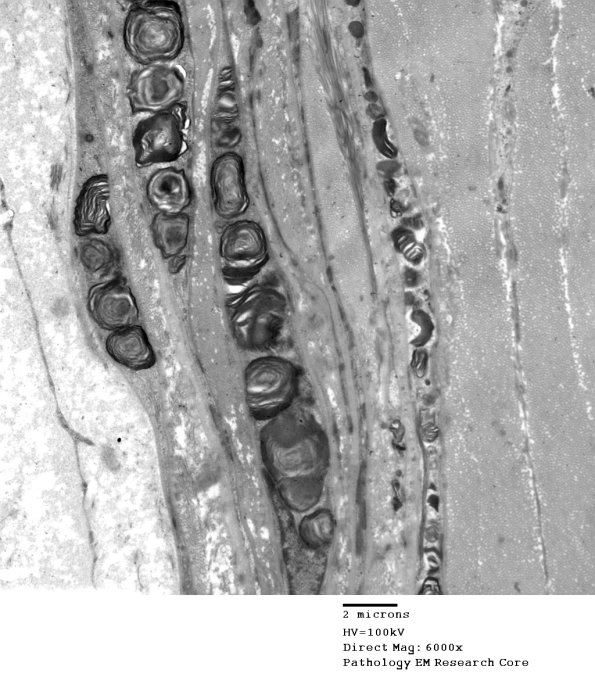

1B6-8 Perineurial inclusions at several magnifications. (electron micrograph)